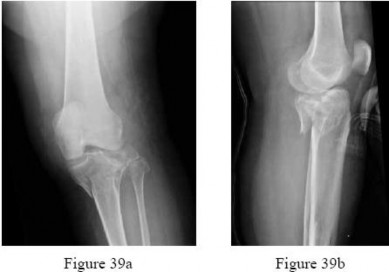

Question 3:

A 22-year-old female soccer player undergoes anterior cruciate ligament (ACL) reconstruction using a bone-patellar tendon-bone (BTB) autograft. During the rehabilitation phase, she is at highest risk for which of the following complications compared to a hamstring autograft?

Correct Answer: Anterior knee pain

Explanation:

BTB autograft is considered the 'gold standard' for ACL reconstruction but is associated with a higher incidence of donor-site morbidity, specifically anterior knee pain and pain with kneeling, when compared to hamstring autograft. Deep infection rates are similar or slightly higher in hamstring autografts.